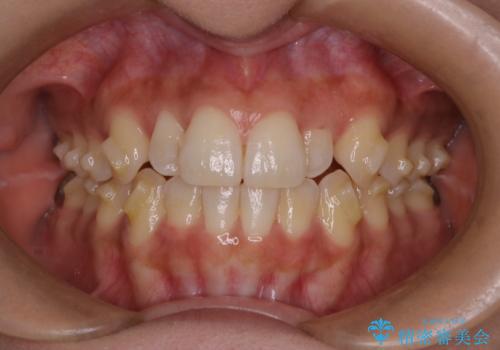

反対咬合と前歯のガタガタを非抜歯で改善

- 患者様は、上下の前歯のガタガタと反対咬合(下の歯が上の歯より前に出ている状態)を主訴として来院されました。診断の結果、抜歯を行わずに治療を進めるため、臼歯を遠心移動させてスペースを作り、IPR(インタープロキシマルリダクション)で歯間を調整する治療計画を立てました。インビザラインを使用して、透明で目立たない矯正装置により、歯列を整えながら噛み合わせも改善することを目標としました。

非抜歯での治療では、限られたスペースの中で効率的に歯を動かす必要があります。本症例では、臼歯を後方に移動させる遠心移動を行い、歯列のガタガタを改善しました。また、IPRを適切に行うことでスペースを確保し、歯根や歯肉への負担を最小限に抑えながら治療を進めました。インビザラインを使用することで、治療中も目立ちにくく、患者様の日常生活への影響を軽減しました。結果として、抜歯を行わずに美しい歯並びと自然な噛み合わせを実現し、患者様には大変満足していただけました。